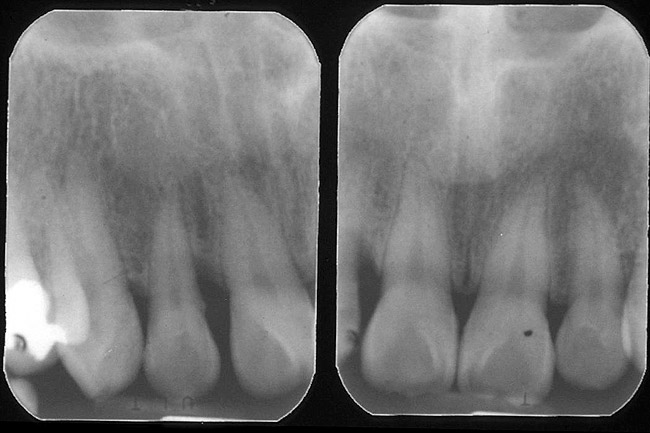

Figure 3  EVALUATION PARAMETERS  The Rule of Thirds: The canal or canal space preparation should not be any wider than one third the mesiodistal root diameter after the endodontic access.

Figure 3